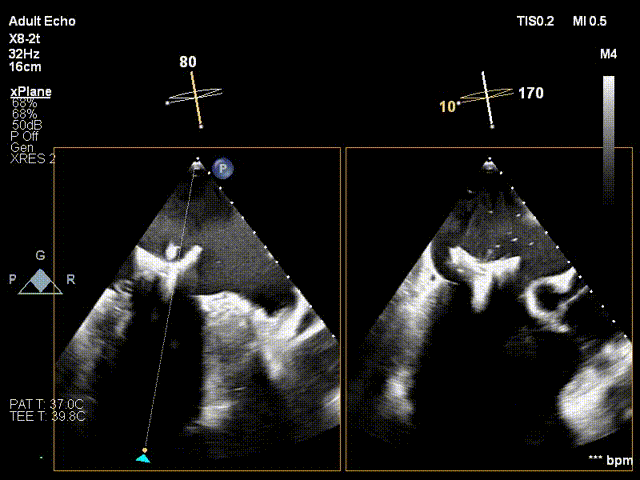

术中超声瓣膜定位

术中超声瓣膜释放

术中介入瓣膜顺利释放

手术在中山医院杂交手术室内完成。手术运用DSA与三维经食道超声心动图监测,通过患者左胸约4cm的小切口经心尖途径将瓣膜输送进病变的二尖瓣部位,在心脏不停跳的状态下快速完成二尖瓣置换,术中几乎无出血、无传导阻滞、无流出道梗阻,血压心率均平稳。